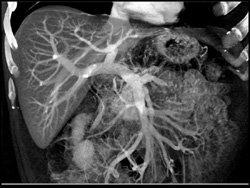

Hepatoma